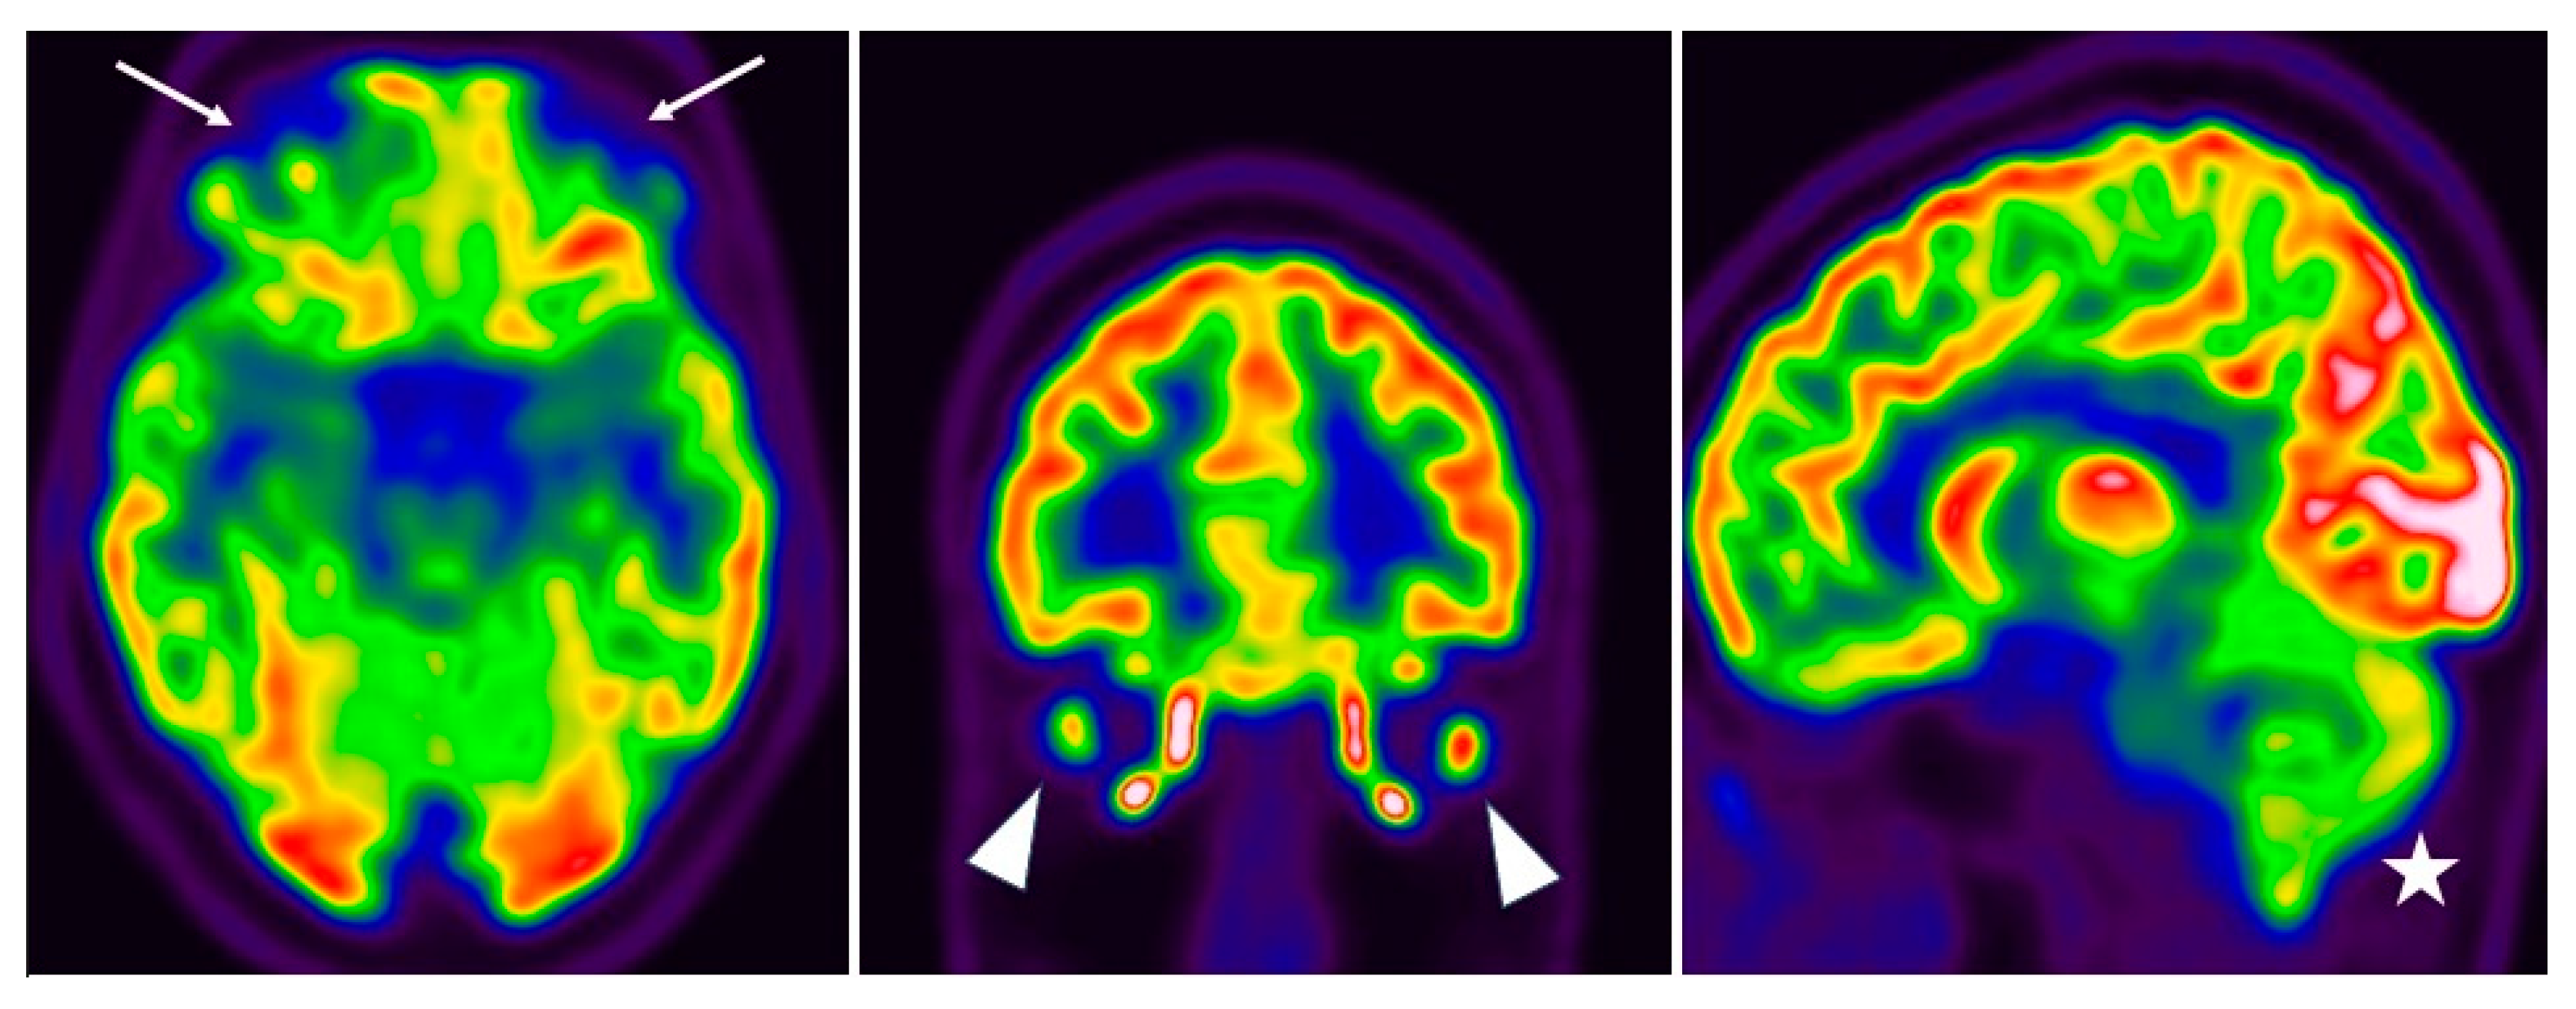

- Guedj, E.; Campion, J.Y.; Dudouet, P.; Kaphan, E.; Bregeon, F.; Tissot-Dupont, H.; Guis, S.; Barthelemy, F.; Habert, P.; Ceccaldi, M.; et al. 18F-FDG brain PET hypometabolism in patients with long COVID. Eur. J. Nucl. Med. 2021, 48, 2823–2833. [Google Scholar] [CrossRef]

- Morand, A.; Campion, J.-Y.; Lepine, A.; Bosdure, E.; Luciani, L.; Cammilleri, S.; Chabrol, B.; Guedj, E. Similar patterns of [18F]-FDG brain PET hypometabolism in paediatric and adult patients with long COVID: A paediatric case series. Eur. J. Nucl. Med. 2021, 49, 913–920. [Google Scholar] [CrossRef]

- Toniolo, S.; Di Lorenzo, F.; Scarioni, M.; Frederiksen, K.S.; Nobili, F. Is the Frontal Lobe the Primary Target of SARS-CoV-2? J. Alzheimer’s Dis. 2021, 81, 75–81. [Google Scholar] [CrossRef]

- Dressing, A.; Bormann, T.; Blazhenets, G.; Schroeter, N.; Walter, L.I.; Thurow, J.; August, D.; Hilger, H.; Stete, K.; Gerstacker, K.; et al. Neuropsychologic Profiles and Cerebral Glucose Metabolism in Neurocognitive Long COVID Syndrome. J. Nucl. Med. 2021, 63, 1058–1063. [Google Scholar] [CrossRef]

- Blazhenets, G.; Schroeter, N.; Bormann, T.; Thurow, J.; Wagner, D.; Frings, L.; Weiller, C.; Meyer, P.T.; Dressing, A.; A Hosp, J. Slow but evident recovery from neocortical dysfunction and cognitive impairment in a series of chronic COVID-19 patients. J. Nucl. Med. 2021, 62, 910–915. [Google Scholar] [CrossRef]

- Ferrucci, R.; Cuffaro, L.; Capozza, A.; Rosci, C.; Maiorana, N.; Groppo, E.; Reitano, M.R.; Poletti, B.; Ticozzi, N.; Tagliabue, L.; et al. Brain positron emission tomography (PET) and cognitive abnormalities one year after COVID-19. J. Neurol. 2023, 270, 1823–1834. [Google Scholar] [CrossRef]